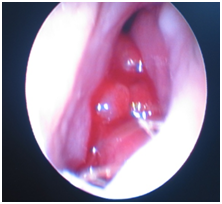

All the patients underwent diagnostic nasal endoscopy under local anaesthesia. Mass was attached to anterior part of the nasal septum in 23 patients (Figure 1) (Figure 2) and in 4 patients, it was arising around the choana (Figure 3).

Figure 3 Nasal endoscopic picture showing the mass filling the choana.